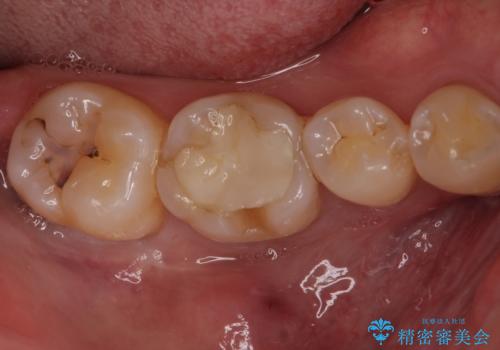

- 他院で行った、古いセラミックが欠けたとのことでご来院された患者様です。

古いセラミックを外すと、無数のヒビが入っており、そこからできた新しい虫歯がありました。

古い材料も虫歯もすべて除去して、根本からやりかえました。

セラミックが欠けるほど強い力がかかっているということは、ご自身の歯も割れている(小さいヒビ等も含む)可能性があります。拡大鏡でしっかり見ながら治療します。